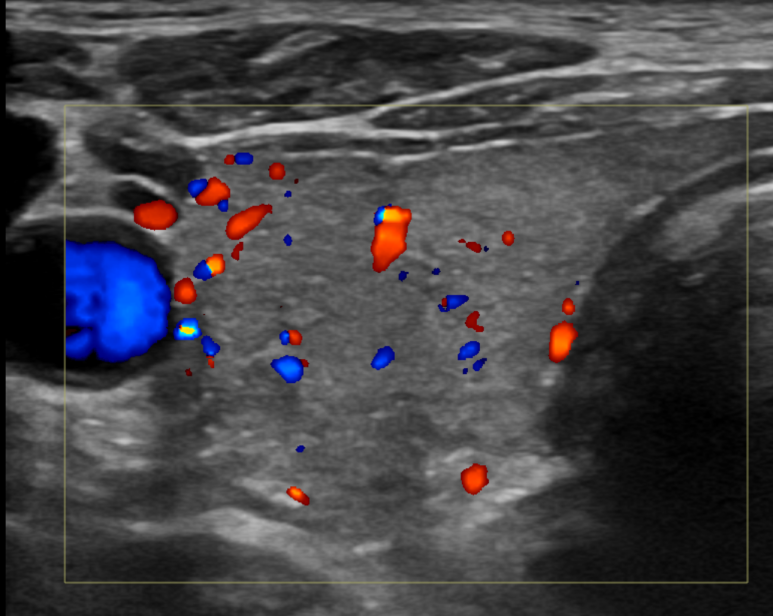

갑상선 초음파이기 때문에 갑상선 초음파를 봅니다만, 검사 전문의 진상 관련 증상이 명확하지 않았기 때문에 예상 밖의 소견이었습니다.

갑상선 표면이 고르지 못하고(Heterogenouse chogenicity) 혈관이 매우 발달되어 있습니다(hypervascularity).

초음파 소견만으로 갑상선 저하 항진인지는 정확한 구분은 어렵지만 갑상선 호르몬의 수치에 이상이 있는 것은 확실합니다.